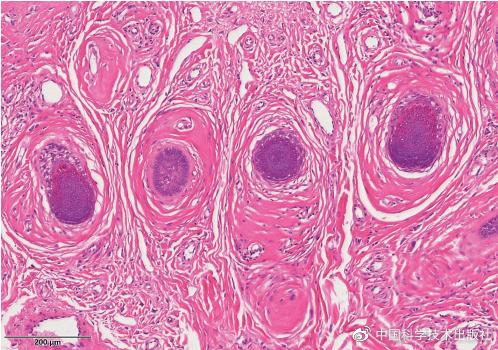

◾ 毛囊周围出现同心圆排列的纤维组织,形成洋葱皮样外观

◾ 纤维组织与周围基质之间有裂隙

毛囊周围纤维瘤:毛囊周围增生的纤维组织形成洋葱皮样外观,并与周围间质间有裂隙

毛囊周围纤维瘤:增生的纤维组织形成洋葱皮样外观

毛囊周围纤维瘤:毛囊周围增生的纤维组织与周围间质间有裂隙